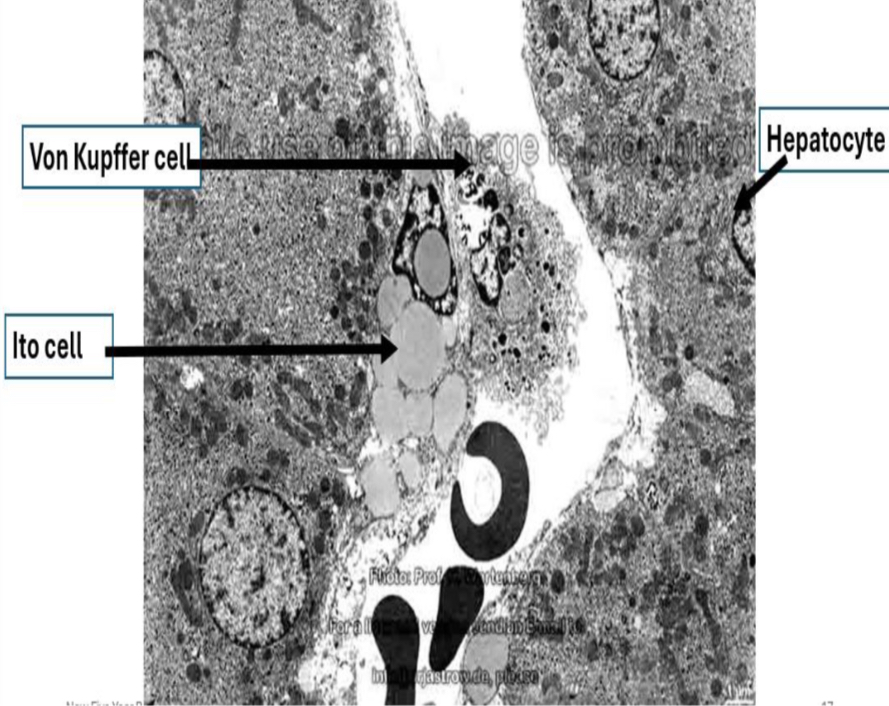

Sinusoids & perisinusoidal space

Identification